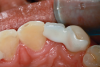

Fig 3. Implants were placed in a 20-year-old female patient in the Nos. 7 and 11 sites with a pontic replacing No. 10.

Fig 4. A 15-year postoperative photograph of the patient in Fig 3 illustrates the significant infraocclusion of the implants compared to the natural teeth. Also, note the blue tissue discoloration over implants Nos. 7 and 11.

A third risk of using an implant to replace a missing lateral incisor is the continued vertical growth of the alveolar bone and eruption of the teeth adjacent to the implant.9,10 Traditionally, it has been taught that an implant can be safely placed when alveolar bone growth is confirmed complete with serial radiographs. However, numerous studies call that rule into question.11-16 Bernard et al evaluated vertical changes in teeth adjacent to implants in a young group of patients (15.5 to 21 years) and in a mature group (40 to 55 years), over a mean time of 4.2 years.17 In the young group, infraocclusion of the implant crowns ranged from 0.1 mm to 1.65 mm, while in the mature group the infraocclusion of the implant crowns ranged from 0.12 mm to 1.86 mm. An example of infraocclusion that occurred in a young implant patient over time is depicted in Figure 3 and Figure 4. Based on classic literature as cited here, it seems prudent to delay the placement of implants in high-risk areas, such as the maxillary lateral incisor region, for as long as possible or perhaps avoid it altogether.